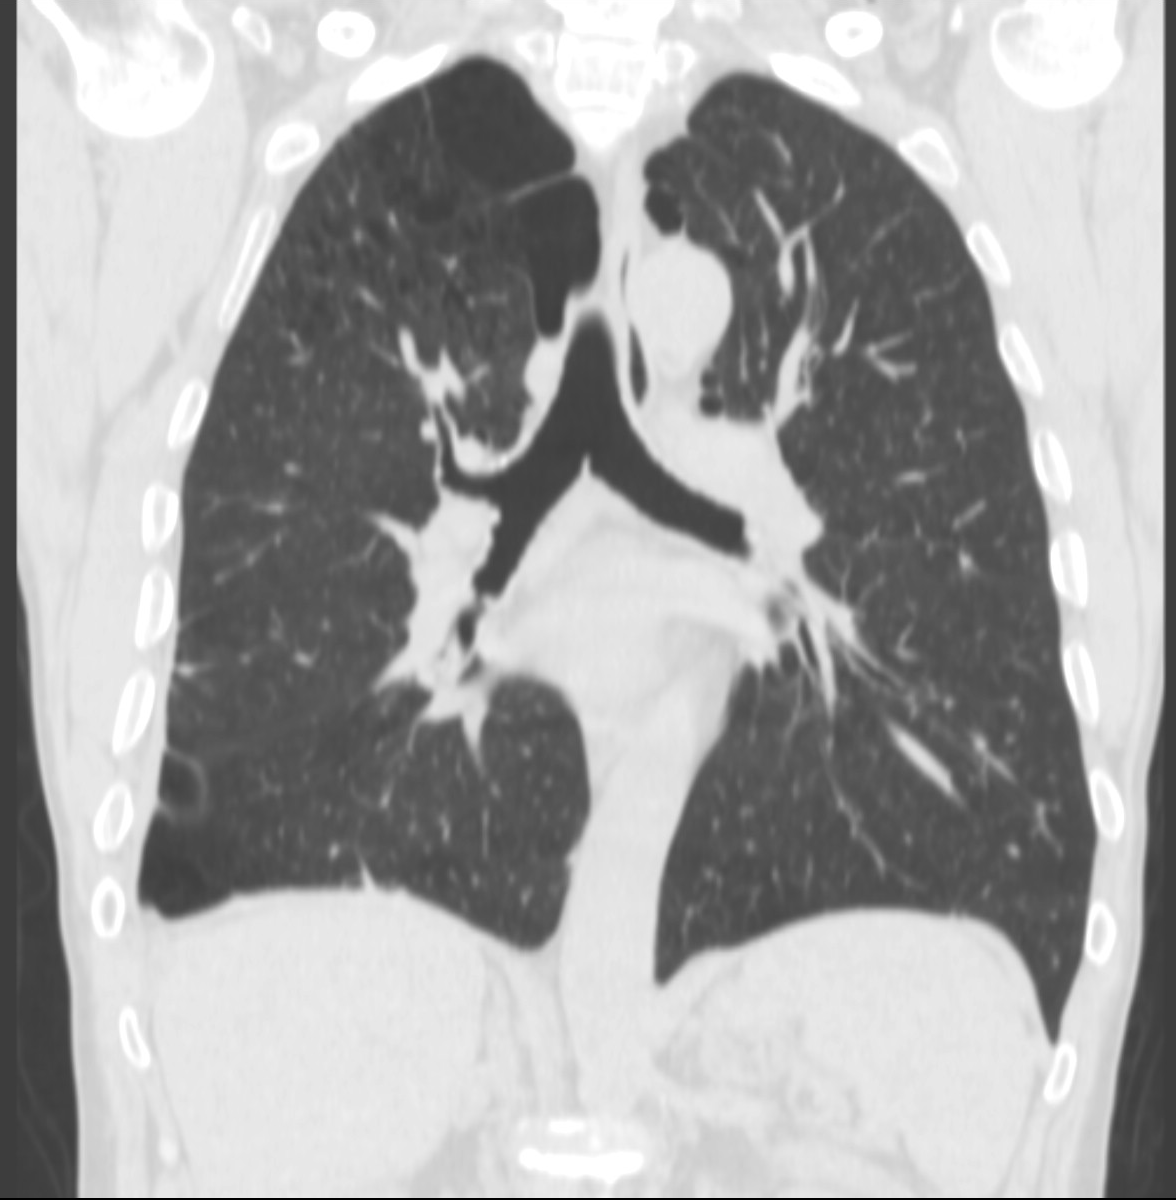

4: Miliary pattern: sarcoidosis, CT, lung window. Axial image and sagittal reformat.

A 67 year old female suffering from COPD. Bilateral rough branching interstitial widening and patchy, miliary nodules with perihilar dominance along the bronchovascular fibres and the fissures.